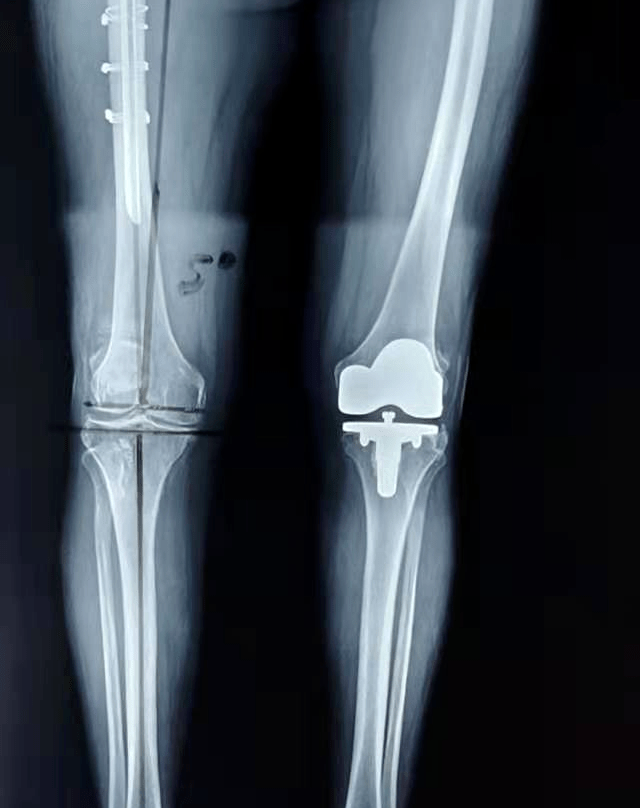

膝关节置换2019.6.18

一周5个膝关节置换创我院历史高峰.

膝关节单髁置换术突破8100例

微创膝关节置换2例